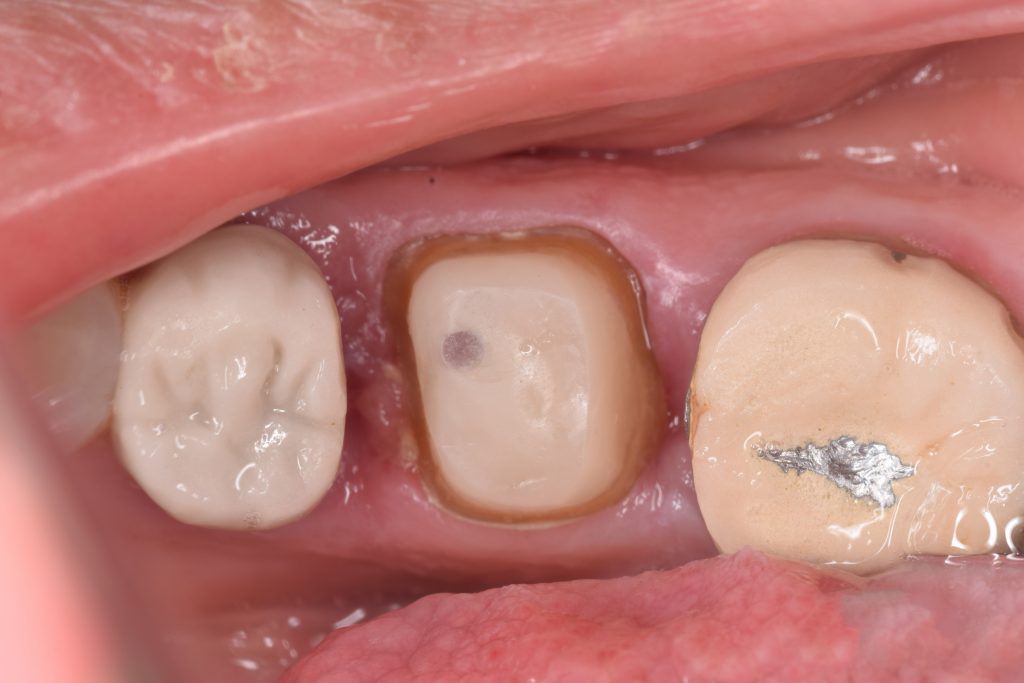

Saving lower first molar by removing the caries , gingivactomy and evaluation the restorability of the tooth